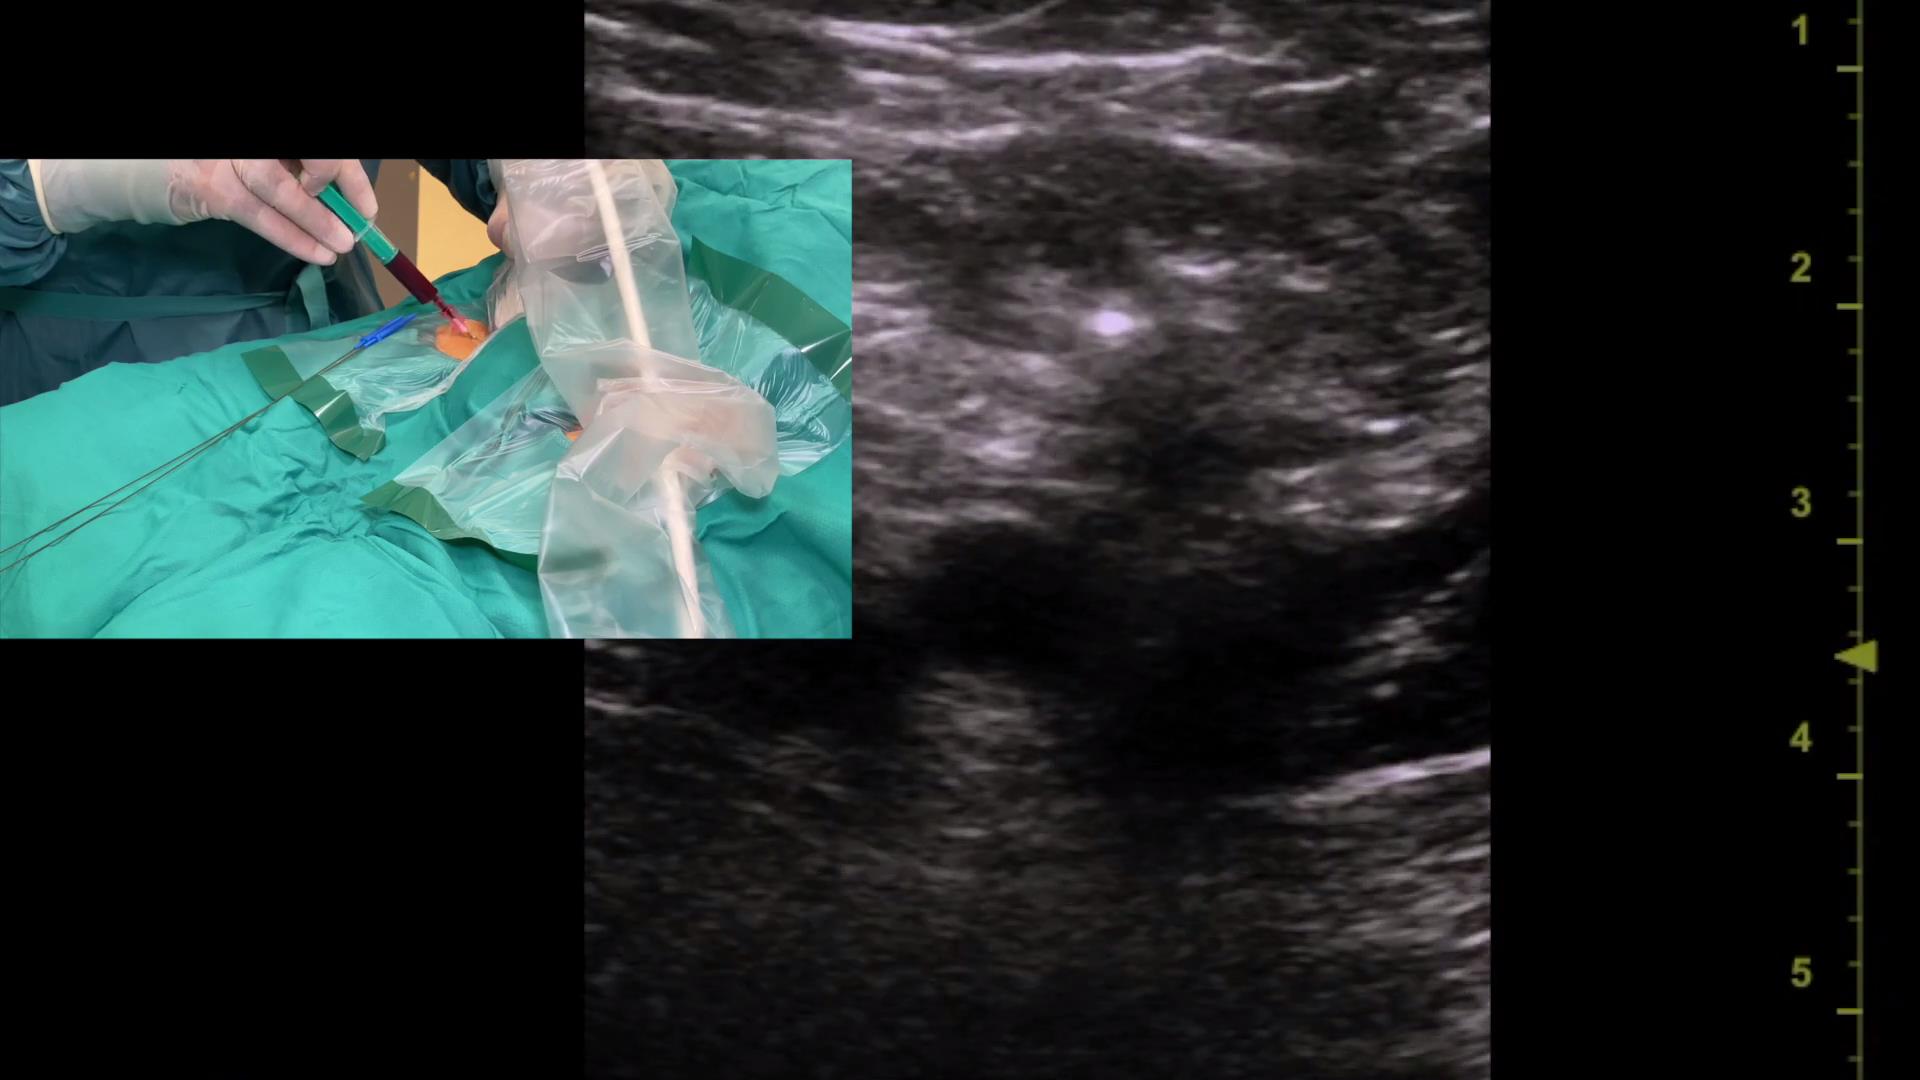

超声引导平面内锁骨下静脉穿刺置管

121 #锁骨下静脉穿刺